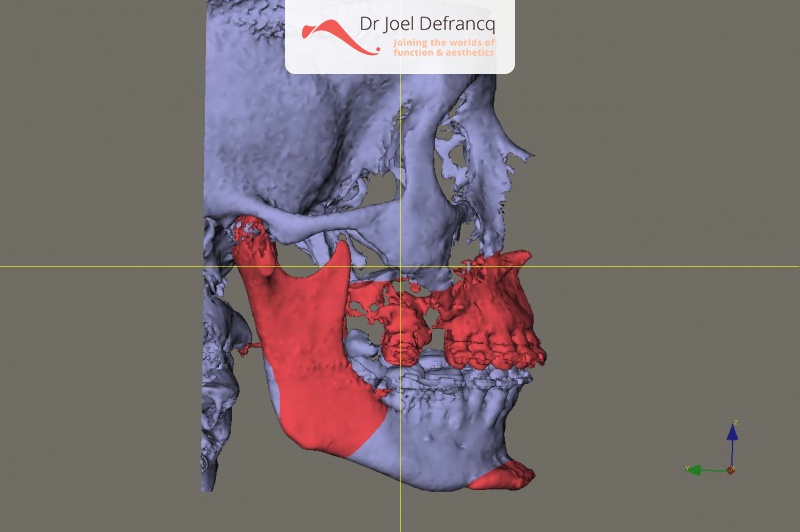

Diagnose van het gezicht

- Te korte bovenkaak

Kaakchirurgie

- Verlenging onderkaak (BSSO)

- Verlenging bovenkaak (Le Fort I)

- Vertikale verlenging bovenkaak (Le Fort I)

- Kinchirurgie

- Redo